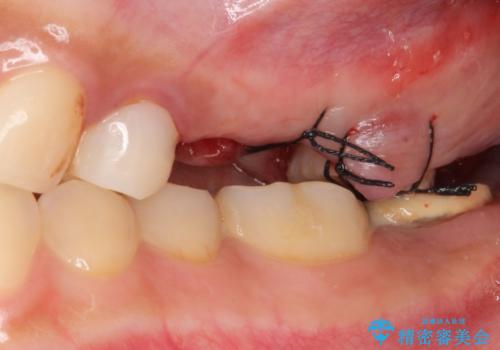

- う蝕により奥歯がボロボロになってしまい、咬むことができないことを主訴に来院された患者様です。

奥歯3本(左上567)はう蝕が深く保存不可能な状態であったため、やむなく抜歯しました。

インプラントも入れ歯も抵抗があるとのご相談により、自家歯牙移植を提案しました。

使っていない親知らず(左上8)を左上7抜歯窩に移植し、支台歯としてブリッジによる補綴治療を行いました。